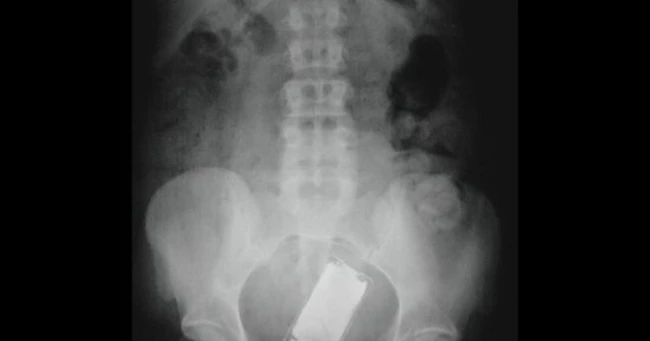

Un iPod a fost descoperit în interiorul unui bărbat

Un alt caz bizar, care l-ar face pe Steve Jobs să se răsucească în mormânt, este cel al unui iPod introdus prin rect.